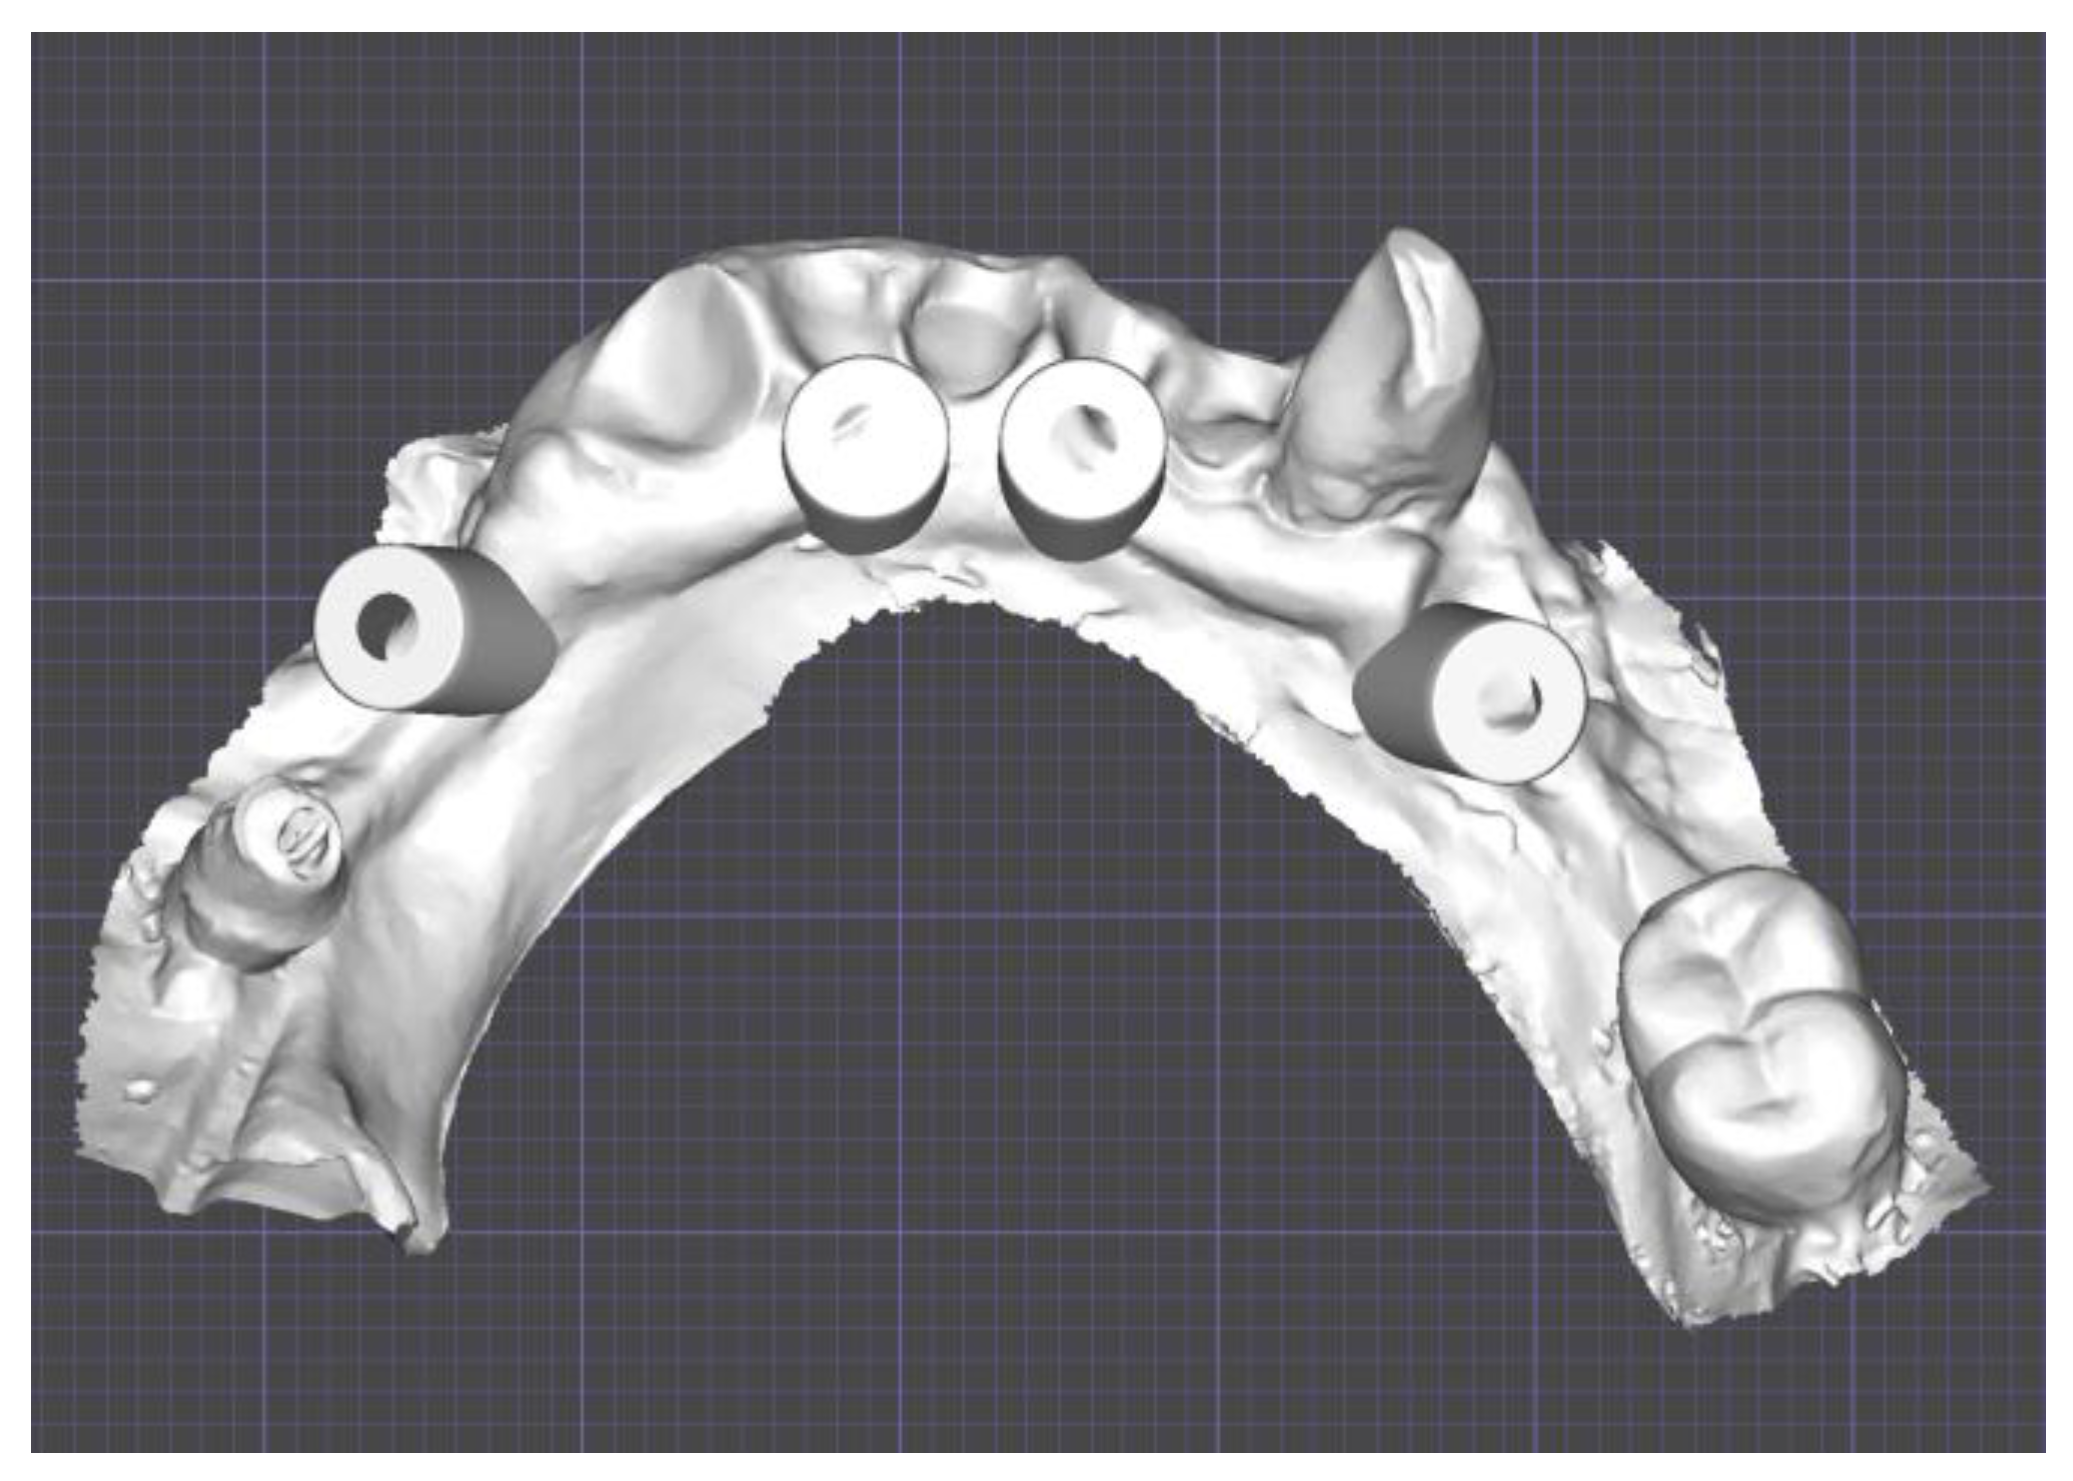

Surgical Guide

2.3. Three-Dimensional Printing

2.4. Surgery